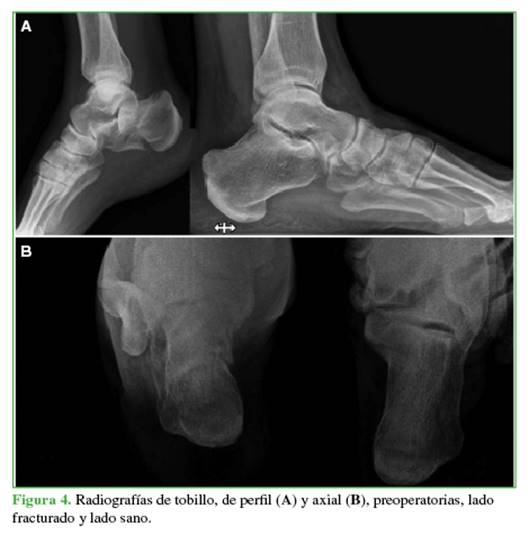

La cantidad y orientación de los tornillos de 6,5/7 mm dependerá de los trazos de fractura. El objetivo de estos es solidarizar la tuberosidad mayor con el cuerpo del calcáneo y con la tuberosidad menor, generando además un “andamiaje” que le brinde estabilidad a la carilla articular posterolateral (Figuras 4-6).

La media del ángulo de Böhler mostró diferencias significativas entre el calcáneo contralateral sano (30,76° ± 5,71°) y la determinación preoperatoria (14,05° ± 6,60°). Sin embargo, las diferencias entre el lado contralateral sano (30,76° ± 5,71°) y los valores posoperatorios, tanto inmediato (29,50° ± 5,96°) como alejado (29,86° ± 6,51°), fueron mínimas. Asimismo, se consideraron los percentiles 25, 50 y 75. Las pruebas de la t de Student para muestras independientes confirmaron que no hubo diferencias estadísticamente significativas entre las mediciones en el calcáneo contralateral sano y los valores posoperatorios inmediato (intervalo de confianza del 95% [IC95%], p <0,571, d = 0,216) y alejado (IC95%, p <0,700, d = 0,147), mientras que sí hubo diferencias significativas con el valor preoperatorio (IC95%, p <0,001, d = 2,708).

La media del ángulo de Gissane resultó con diferencias entre el calcáneo contralateral sano (119,03° ± 6,99º) y el valor preoperatorio (110,31º ± 10,01º). Sin embargo, entre el lado contralateral sano (119,03° ± 6,99º) y las determinaciones del posoperatorio inmediato (118,85 ± 7,54) y el alejado (119,00 ± 7,43), la diferencia no fue significativa. Las pruebas de la t de Student para muestras independientes confirman que no hubo diferencias estadísticamente significativas entre el calcáneo contralateral sano y los valores posoperatorios inmediato (IC95%, p = 0,948, d = 0,0248) y alejado (IC95%, p = 0,992, d = 0,004), mientras que sí hubo diferencias significativas con el valor preoperatorio (IC95%, p = 0,013, d = 1,010).

La media de la longitud del calcáneo arrojó diferencias mínimas entre el calcáneo contralateral sano (77,61 ± 8,25), el valor preoperatorio (76,01 ± 8,47), los valores posoperatorios inmediato (78,26 ± 8,01) y alejado (76,99 ± 7,56). Las pruebas de la t de Student para muestras independientes confirman que no hubo diferencias estadísticamente significativas entre el calcáneo contralateral sano, el valor preoperatorio (IC95%, p = 0,617, d = 0,191) y los valores posoperatorios inmediato (IC95%, p = 0,835, d = -0,080) y alejado (IC95%, p = 0,836, d = 0,078).

La media del ancho del calcáneo mostró diferencias entre el calcáneo contralateral sano (36,94 ± 4,09) y el valor preoperatorio (44,13 ± 9,36). Sin embargo, entre el lado contralateral sano (36,94 ± 4,09º) y los valores posoperatorios inmediato (39,17 ± 4,77) y alejado (38,99 ± 5,16), la diferencia fue poca.